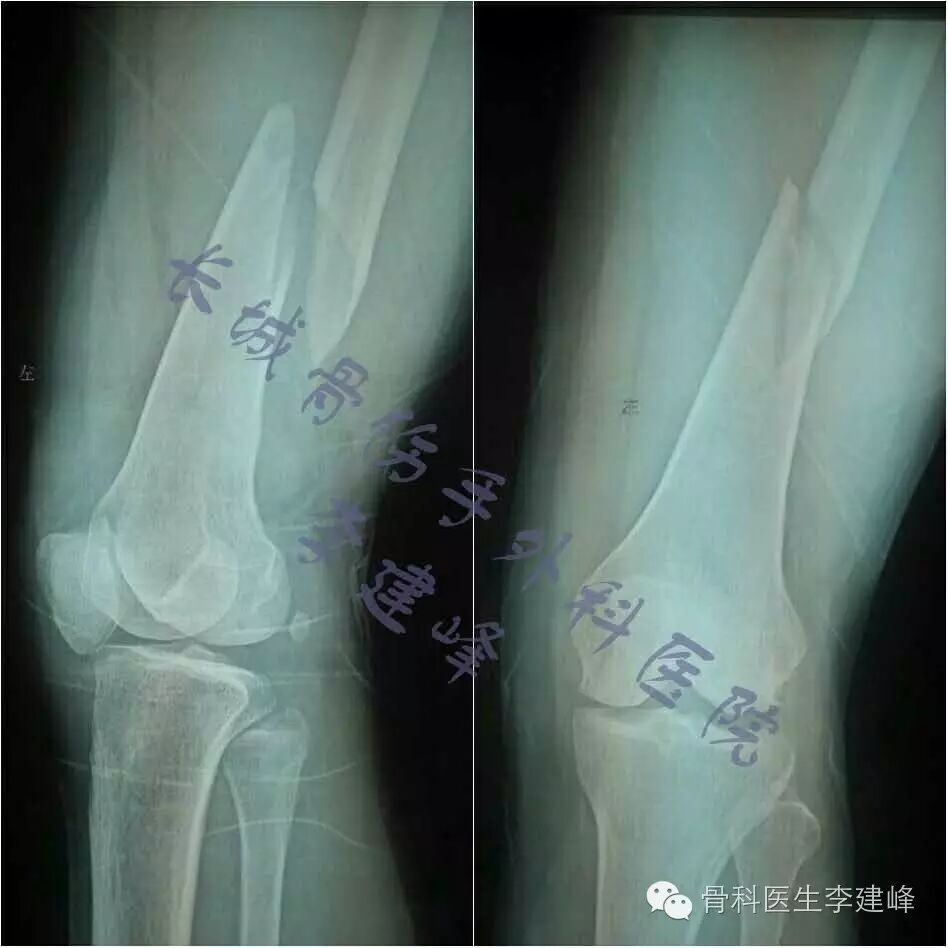

Four case:

术前